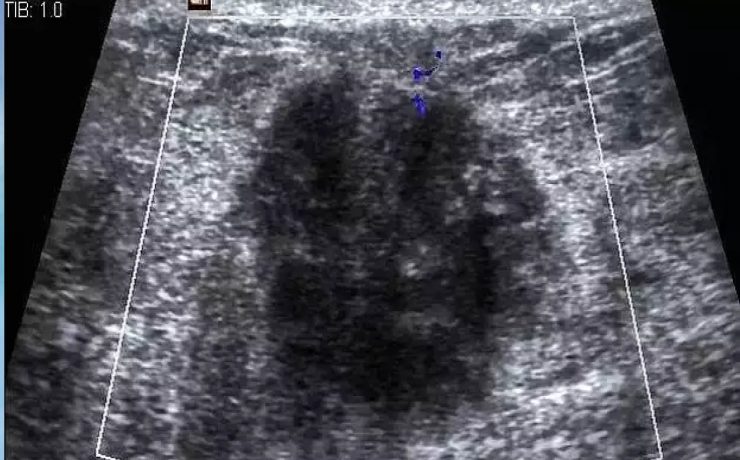

El desarrollo embrionario y fetal del riñón y de las vías urinarias es un proceso biológico extraordinariamente complejo. La formación del riñón definitivo se inicia a partir de la quinta semana de vida intrauterina y su desarrollo depende de la interacción de sus dos compartimientos tisulares; la yema ureteral que